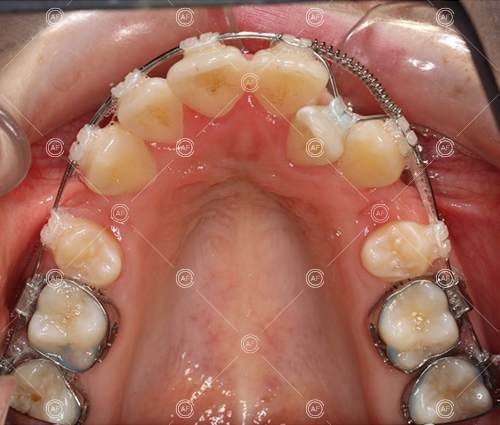

Treatment progressed by starting with thin, flexible nickel titanium archwires of a round diameter, transitioning to a rectangular nickel titanium archwire before eventually working up to a working archwire (1925 stainless steel).

Residual space from the extractions were closed using upper and lower nickel titanium closing coils. Class 2 elastics were used to facilitate space closure in order to gain class 1 buccal segments.